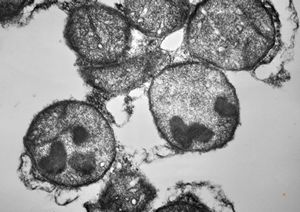

F,32y. | M. Gaucher